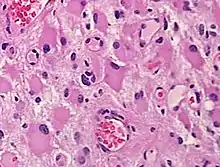

Gemistocytes are glial cells that are characterized by billowing, eosinophilic cytoplasm and a peripherally positioned, flattened nucleus. Gemistocytes most often appear during acute injury; and eventually, shrink in size.[1] They are usually present in anoxic-ischemic brains, which occurs when there is a complete lack of blood flow to the brain. The human brain contains many cells that can impact gliosis, including endothelial progenitors, fibroblast lineage cells, different types of inflammatory cells, and various types of glia and neural-lineage progenitor cells, which include astrocytes.[2] Gliosis occurs when the body creates more, or larger, glial cells that cause scars in the brain that impact body functions. The human body has many body functions to maintain homeostasis because gliosis can occur immediately upon injury. Anoxic-ischemic brains usually occur in patients who have had cardiac arrest and prolonged attempt at cardiopulmonary resuscitation.[2]

When present in anoxic-ischemic brains, gemistocytes are regularly encountered in glial neoplasms, also known as glioma, which is a type of tumor that occurs in the brain and spinal cord. Usually, gliomas begin in the glial cells that surround the nerve cells to help them function. Many gliomas exhibit cells that do not exist in normal brain tissue and are not seen in glial differentiation.[1] Of these gliomas are astrocytomas, which is a type of cancer that occurs in the brain or spinal cord. The main role of astrocytes is to maintain brain homeostasis and neuronal metabolism. When the astrocytes become activated, they begin to respond to damage.[3] Astrocyte activation, known as astrogliosis, responds to neurological trauma, infections, degradations, epilepsy, and tumorigenesis. Each neurological insult plays a major role in astrocyte activation and response to that specific damage. In some astrocytomas, the number of gemistocytes is extremely overwhelming, terming it a “gemistocytic astrocytoma.” Not only are gemistocytic cells present in astrocytomas, but they are also found in various glial tumor cells; for example, oligodendrogliomas, mixed oligoastrocytomas, glioblastomas, and pleomorphic xanthoastrocytomas. Gemistocytes are known to have a large cytoplasmic mass, long, branching processes, and increased cytoplasmic filaments.[1] The cytoplasm of gemistocytes stains positive for glial fibrillary acidic protein, GFAP. While the intermediate filaments in gemistocytes are diffused throughout the cytoplasm, which indicates cellular disintegration. Within these different tumor types, the term “mini-germistocytes” is used for smaller gemistocytes, that are usually found in oligodendroglial tumors. Mini-germistocytes are found to have a very ordered arrangement of filaments throughout the cytoplasm, but may also transform into the end-state morphology of the larger gemsitocytic cells. Studies have suggested that both classic gemistocytes and mini-gemistocytes show similar genetic variation to non-gemistocytic tumor cells.[4] Mini-germistocytes, usually found in oligodendroglial tumor cells, express gliofibrillary oligodendrocytes, or GFOCs, which are capable of transforming the mini-gemistoctyes into larger gemistocytes.